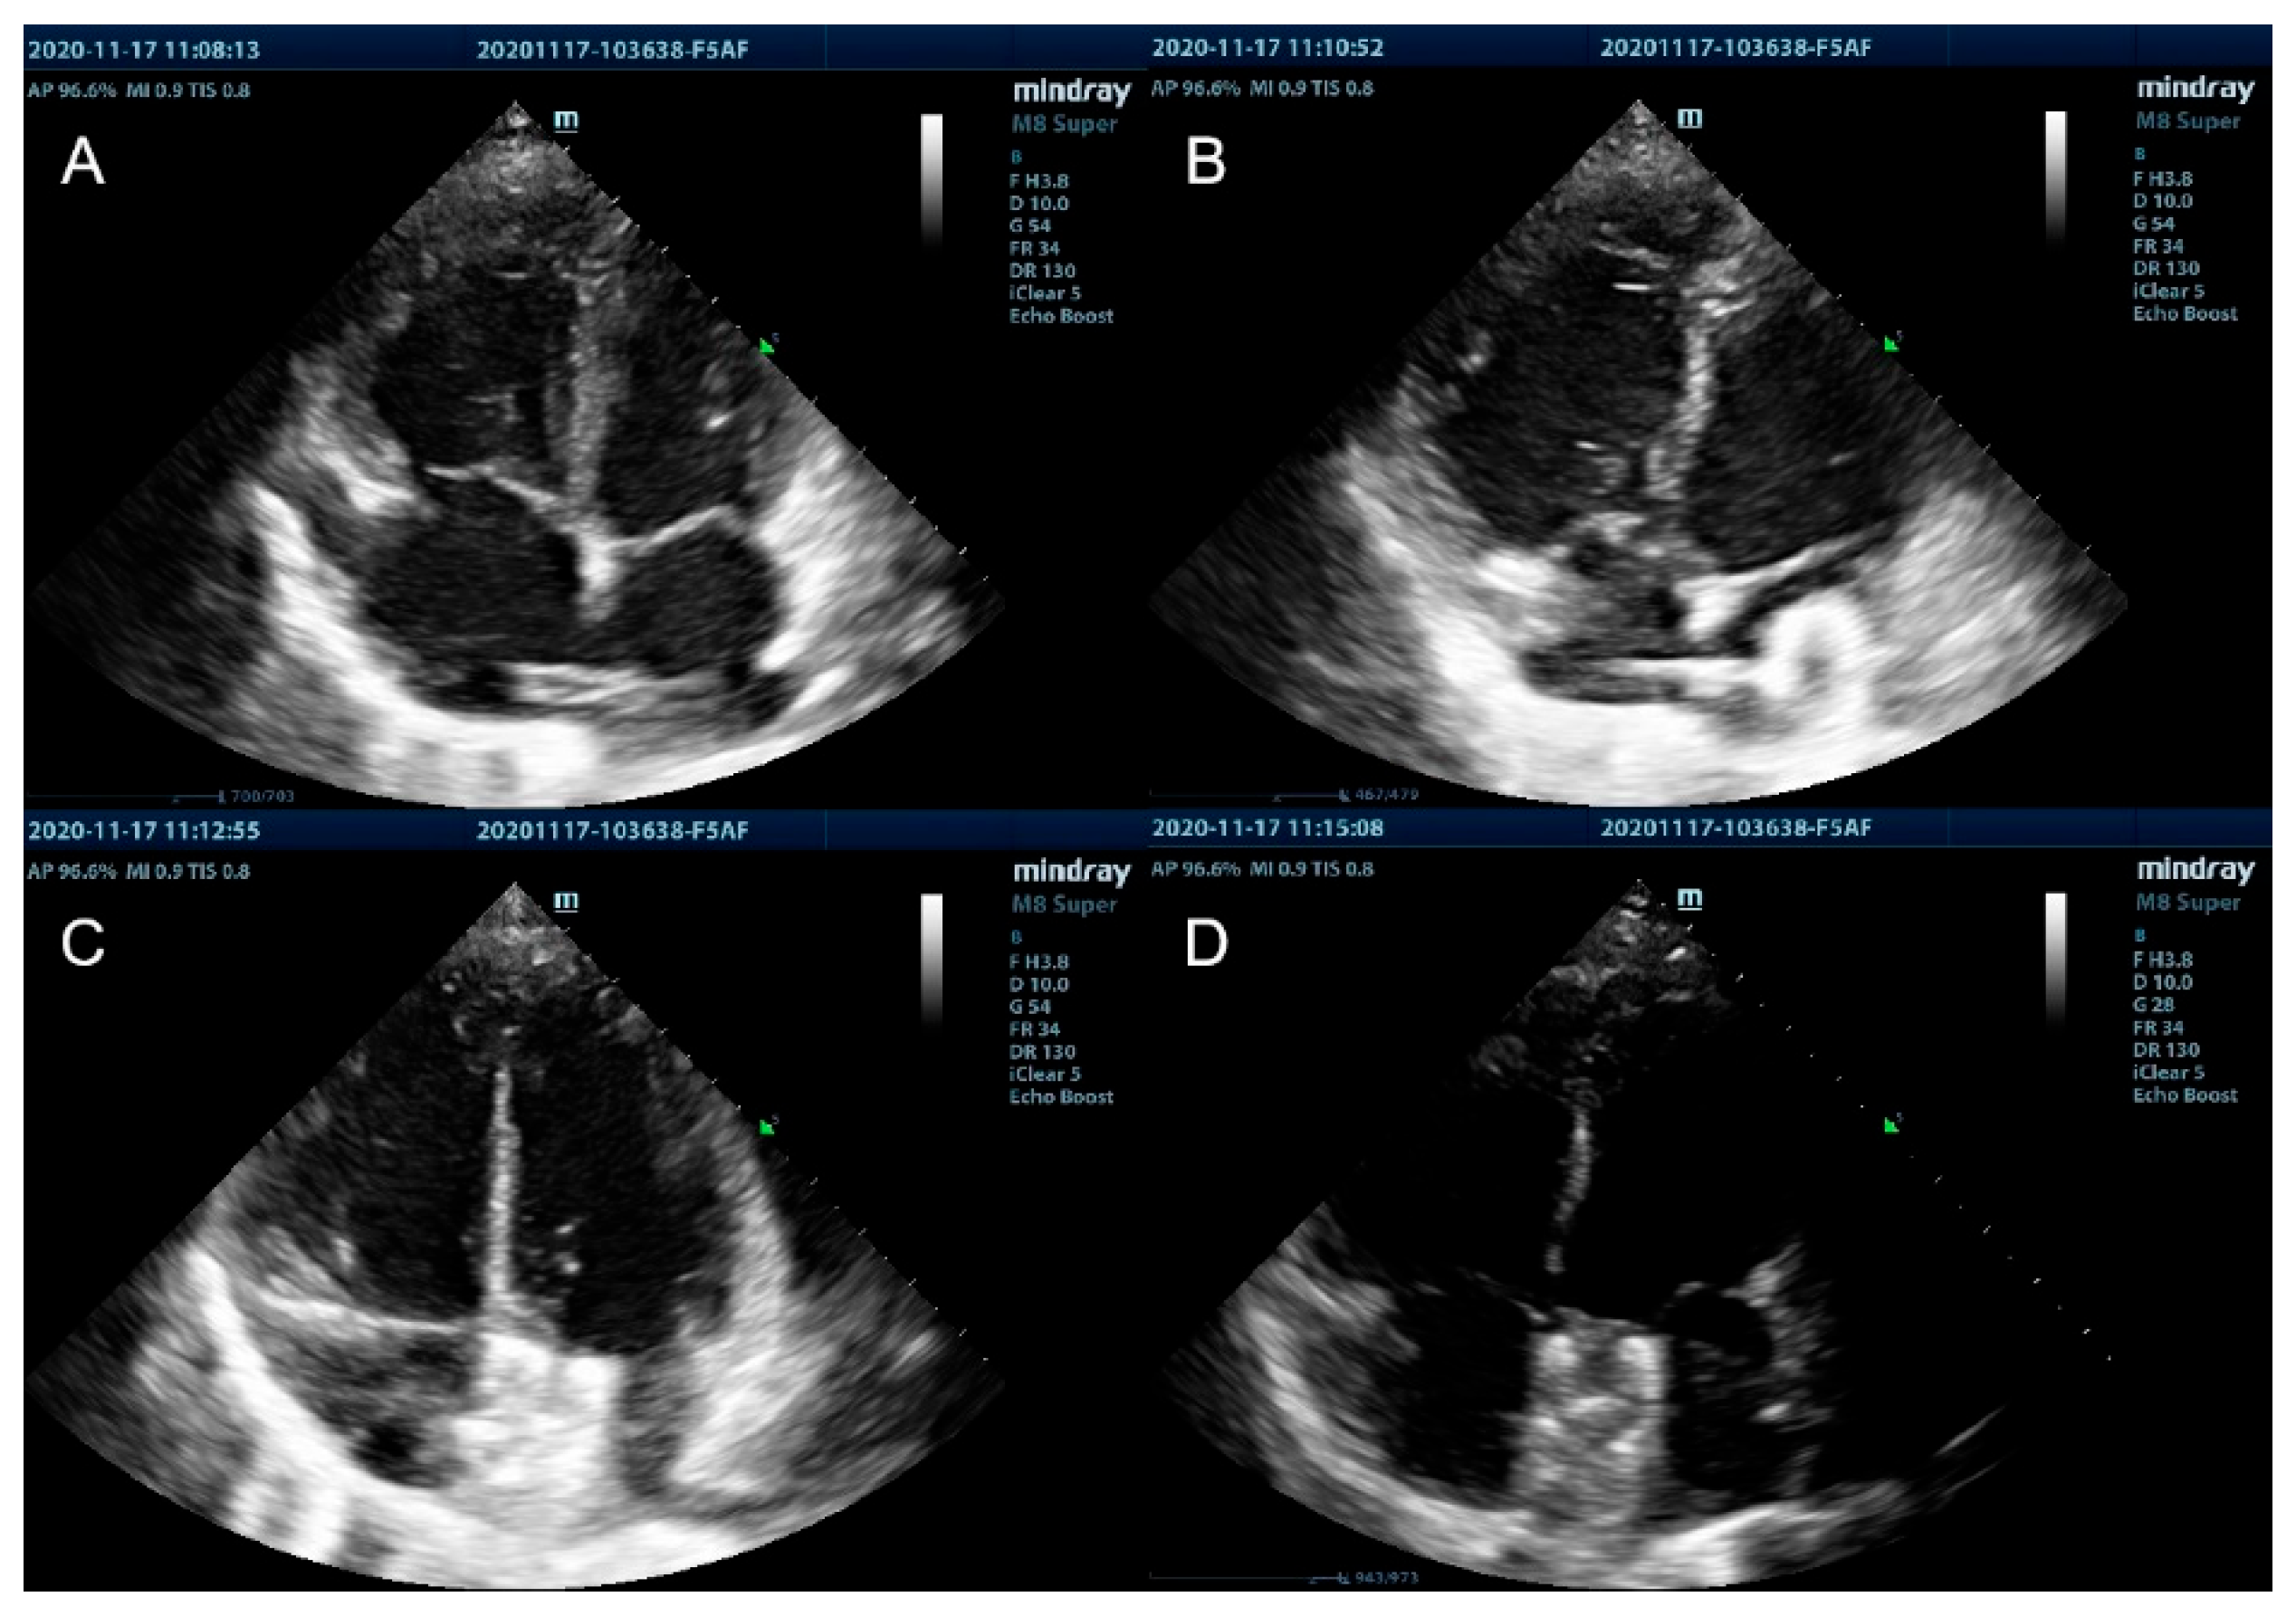

The length was marked on a 6Fr multifunctional catheter to indicate the distance from the puncture site to the right atrium, before being advanced through the inferior vena cava to the right atrium. Under the direction of real-time TTE, adjusting the angle, direction, and depth of the tip of the multifunctional catheter, it entered into the left atrium through the ASD. Feed the stiffened guide wire along the catheter, fix the guide wire in the left lower pulmonary vein, withdraw the catheter, feed the 8Fr delivery sheath along the stiffened guide wire to the left atrium, and withdraw the delivery sheath core and the guide wire. Under the guidance of TTE, the 16 mm occluder was pushed into the sheath. The left and right atrial disks were released in sequence. The shape of the occluder, position, and atrioventricular valve function were assessed by TTE (Fig. 4). Finally, the delivery sheath was removed, and compression bandages were applied. The operation time lasted 30 min. Aspirin was given (3–5 mg/kg, orally) every day for 6 months. The girl recovered and was discharged from the hospital 3 days after the intervention. There were no major cardiovascular-related complications.

Figure 4: (A) Apical four-chamber view of the heart revealing the multifunctional catheter was advanced through the ASD to the left atrium. (B) Under the guidance of real-time TTE, the left atrial disc of the occluder was opened and pulled back parallel to the atrial septum. (C) Under the guidance of real-time TTE, the right disc was sequentially opened to close the ASD. (D) After checking the occluder’s immobility and the possible presence of a residual shunt, the occluder was released.